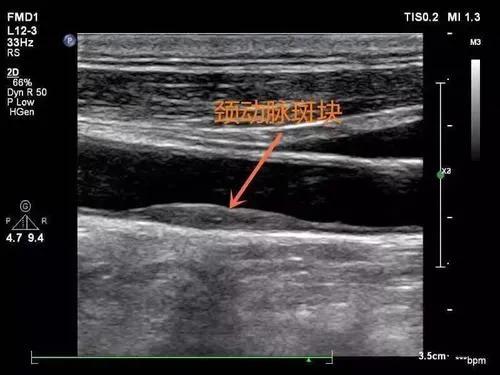

隨著體檢頸動脈超聲的普及,查出頸動脈斑塊的朋友也不在少數,調查顯示,我國40歲以上的人動脈斑塊檢出率是40%,60歲以上的人動脈斑塊檢出率是90%。眾所周知,頸動脈斑塊+高血壓是腦卒中的獨立危險因素,查出斑塊後除了服用調節血脂的藥物,飲食上面我們應該如何配合醫生達到更好的效果呢?作為考取了健康管理師和營養師的我,依據營養師教材所給建議,整理篩選後給出如下建議:

首先,我們要了解頸動脈斑塊形成的高危因素是老齡、長期吸菸和高血壓導致的血管內膜損傷及動脈壁的機械性損傷、高血脂引起血液脂性成分加速沉積到血管壁,再加之久坐不動等多方面共同作用所致,所以我們的飲食當中就應該儘量降低血脂和避免導致血壓升高的因素,該飲食模式對合並冠心病的朋友也大有裨益。